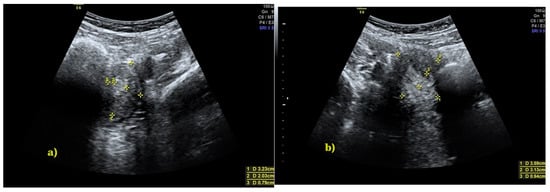

2. Case Presentation